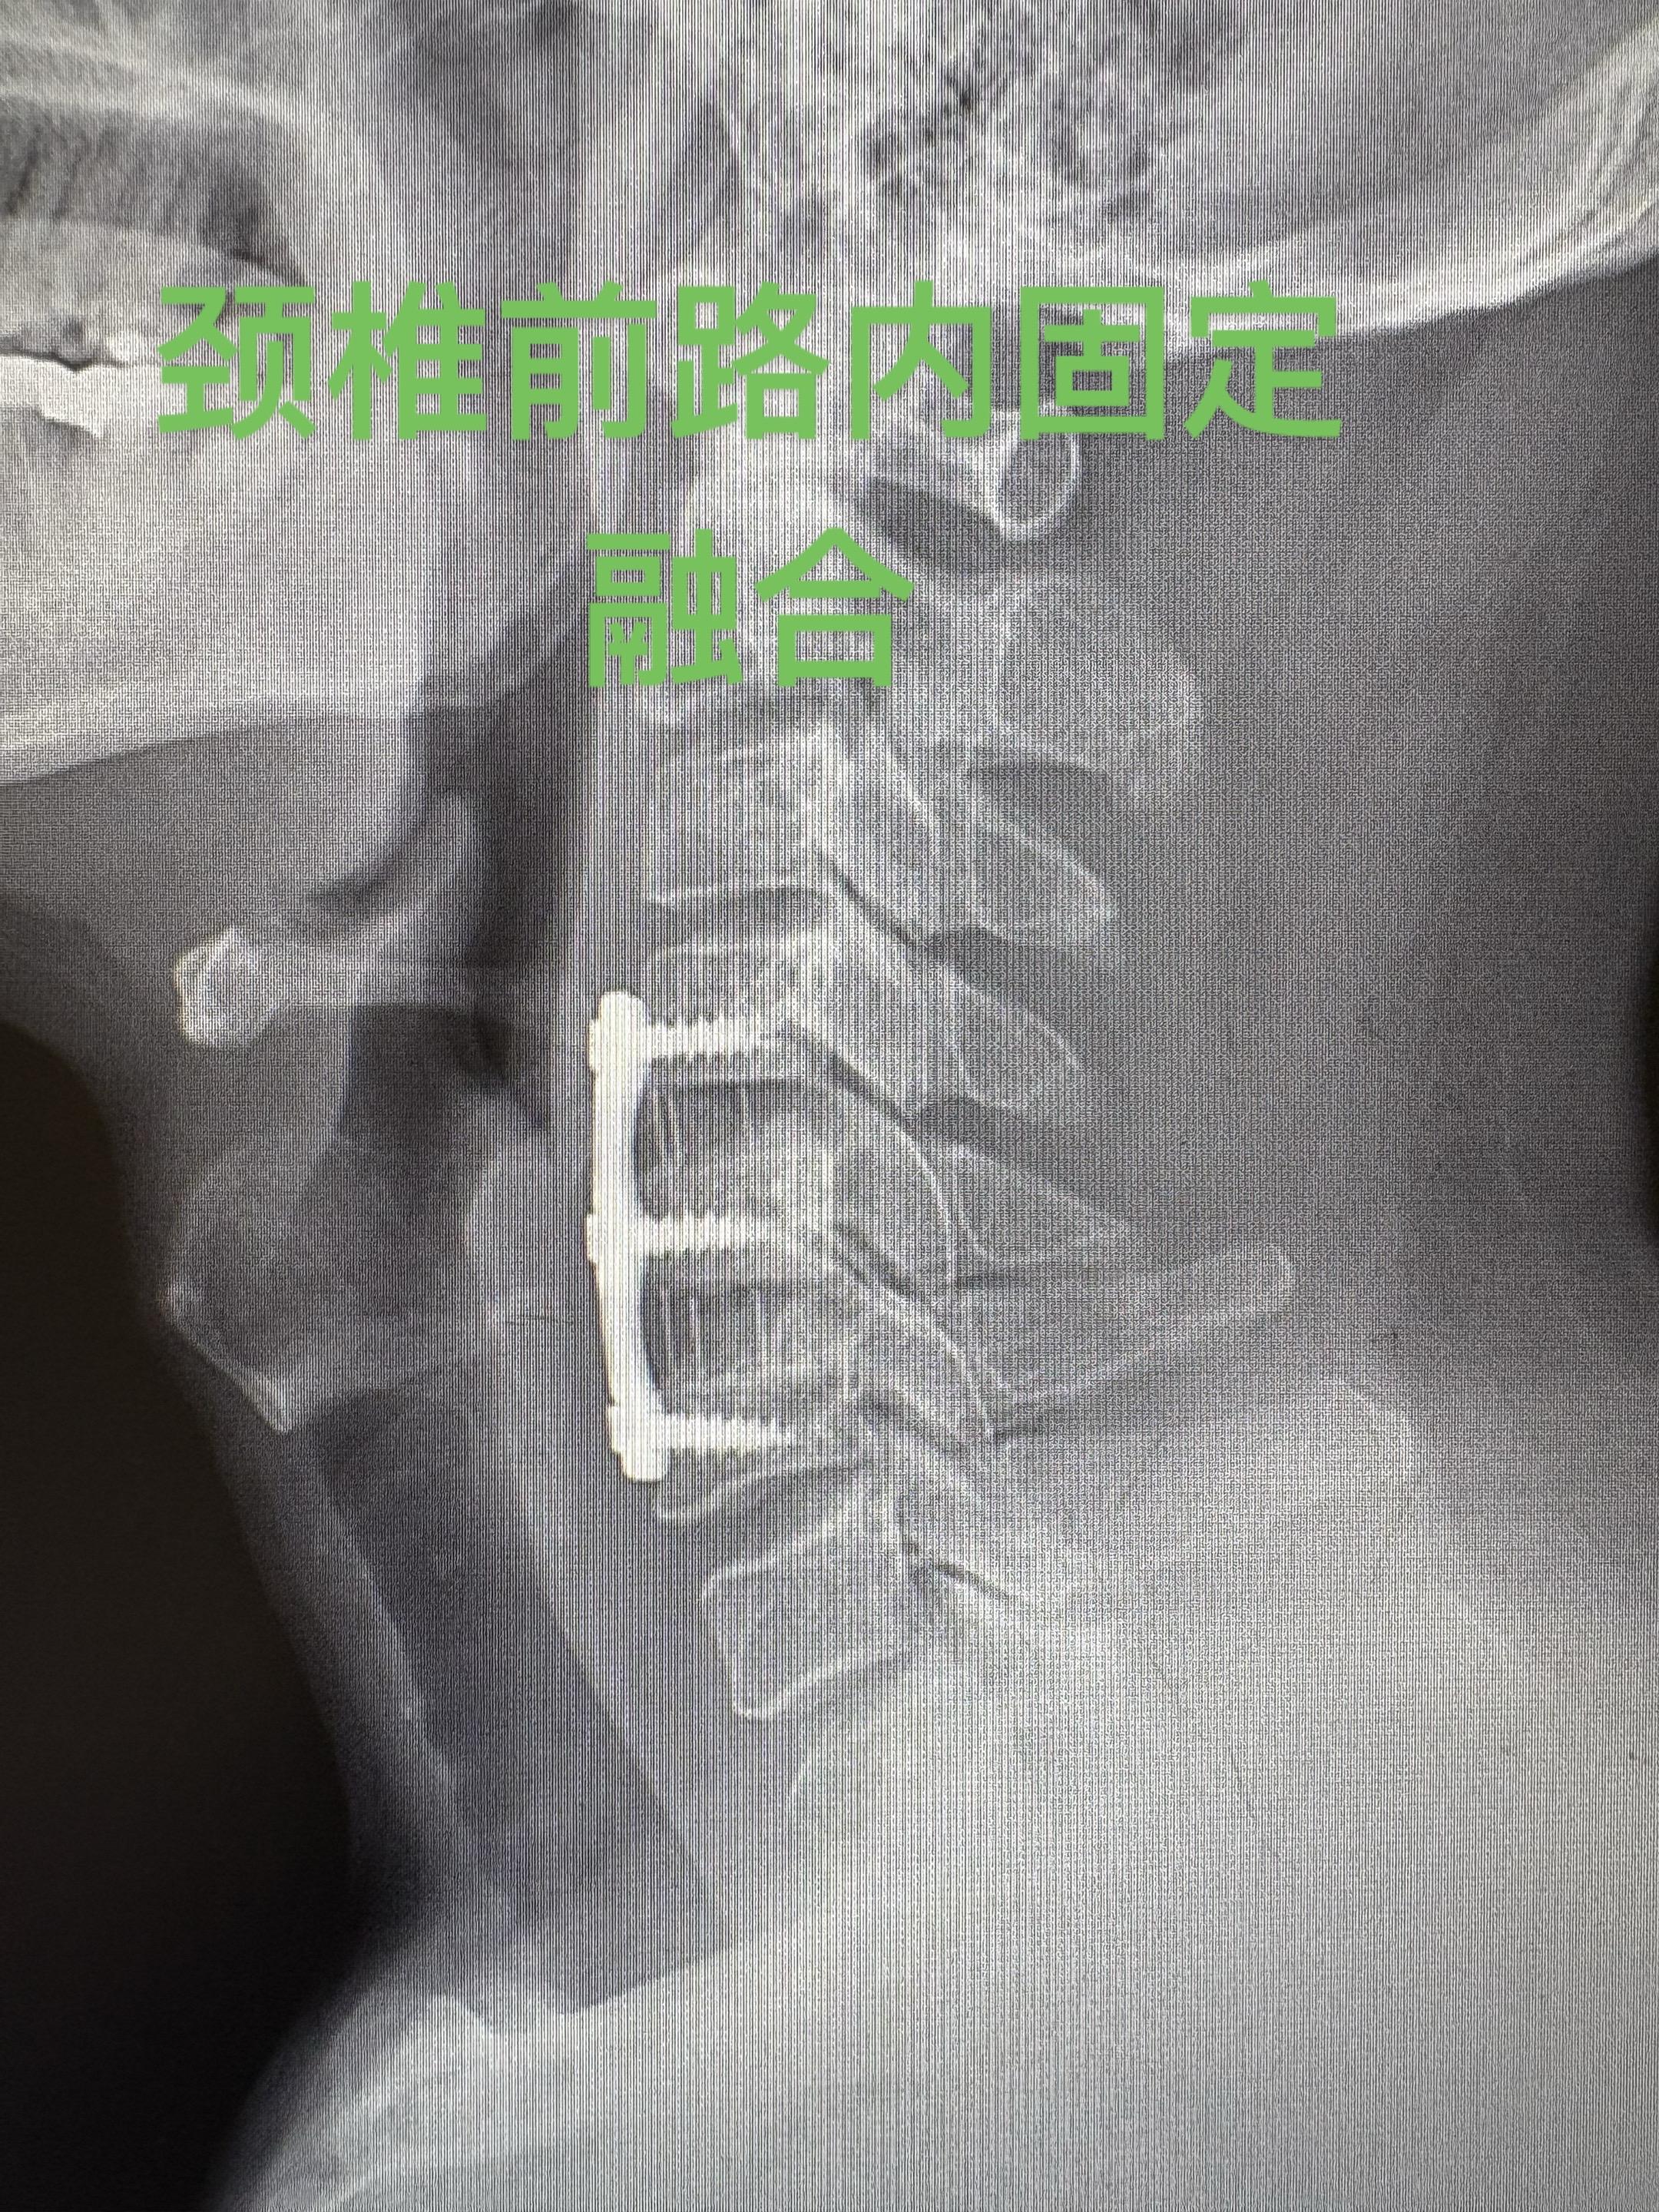

颈椎病手术后后一年复查。手术做完一年,患者手术前的踩棉花感已经消失,但有时候会有一侧肢体的无力感。手术很顺利,术后复查的磁共振以及X光片也很满意。病人唯一的遗憾就是没有及时发现,当时当腰椎间盘突出治疗浪费了不少时间。劝慰患者放松心态,一般此种症状两年之内还是会不断地改善。